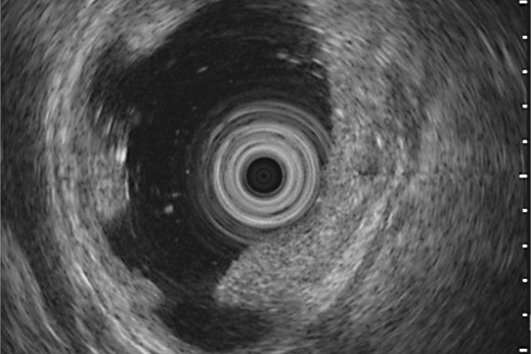

Endoscopic ultrasound (EUS) is a specialized medical procedure that combines endoscopy and ultrasound imaging to visualize and evaluate the gastrointestinal tract and surrounding structures. It is commonly used for diagnostic purposes to assess conditions such as gastrointestinal cancers, pancreatic disorders, and abnormalities in the liver or adjacent organs.

During an EUS procedure, a thin, flexible tube called an endoscope is inserted through the mouth or rectum, depending on the area being examined. The endoscope has a small ultrasound probe at its tip, which emits high-frequency sound waves to create detailed images of the organs and tissues surrounding the digestive tract.